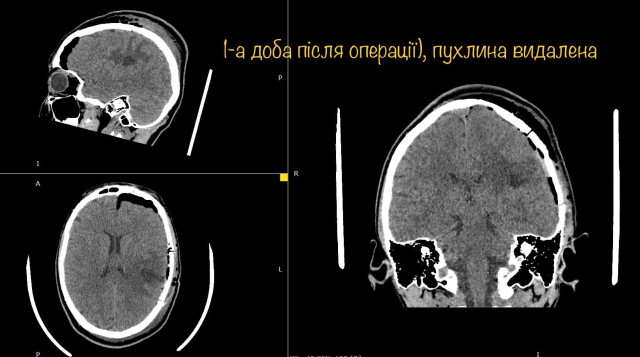

І хоча пухлина, як розповідає Михайло Ловга, знаходилась всього в кількох міліметрах від центру мови, і лікарі ледве-ледве знайшли безпечну ділянку мозку, через яку вдалось видалити пухлину – результат лікування чудовий. Діана вже через годину після операції вільно розмовляє, звичайно рухає усіма кінцівка і ні на що не скаржиться.